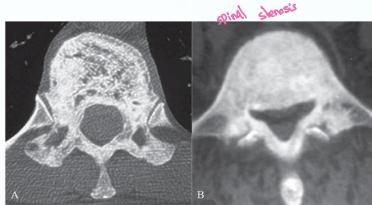

- CT Scan: Shows bony structures in detail